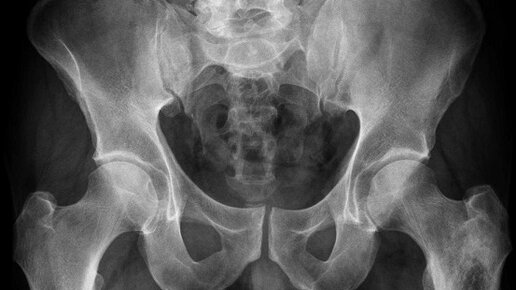

Рентгенография костей таза, что это? Это стандартный 2-х мерный рентгеновский снимок. Обычно снимок делают в одной прямой проекции, при этом пациент располагается лежа на спине. Но в некоторых случаях, на усмотрение врача, возможны дополнительные проекции. Что можно увидеть на исследовании? Данный снимок позволяет оценить: а так же выявить травмы, патологические изменения, аномалии развития. Показания к проведению исследования: Особенности подготовки к процедуре: Для того, что бы получить четкий, хороший снимок, необходимо произвести специальную подготовку...